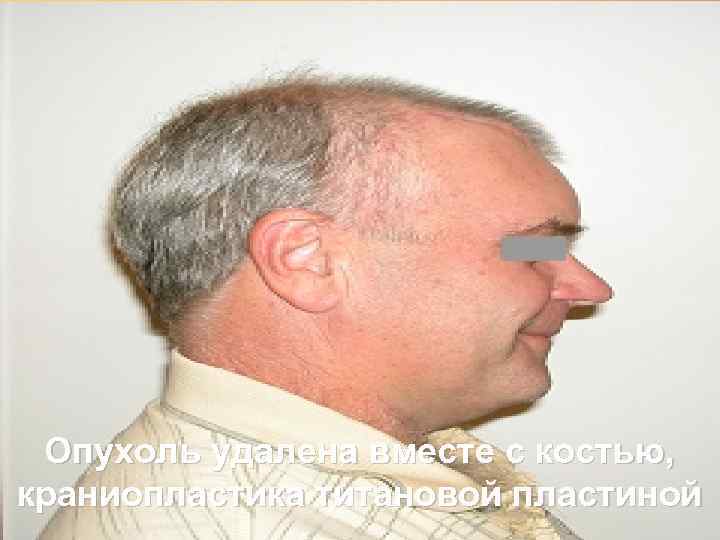

Опухоль удалена вместе с костью, краниопластика титановой пластиной 65

Больной после операции 66